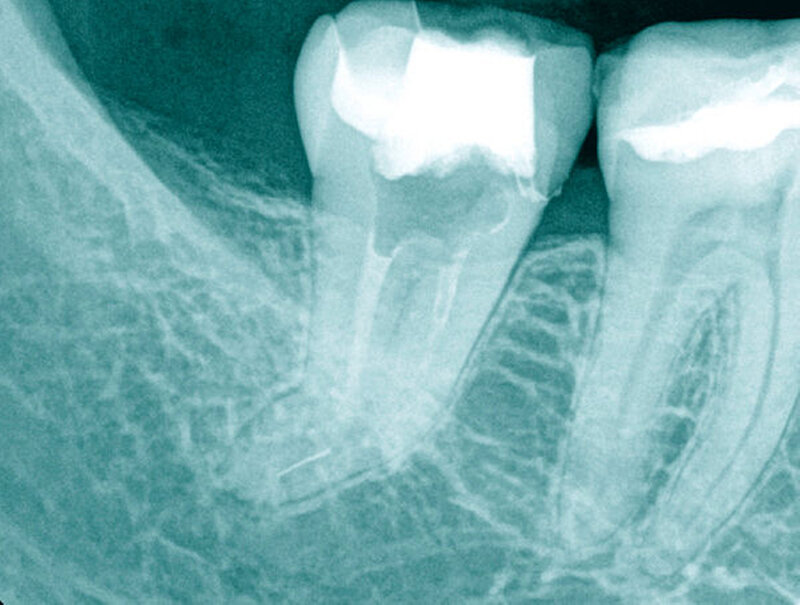

Fallbeispiel 1 (Abbildung 1)

Aufgrund einer fortbestehenden mikrobiellen Infektion wurde eine endodontische Revision am Zahn 26 erforderlich. Unter vergrößerter Sicht mit einem Dentalmikroskop ließen sich drei in Einstifttechnik gefüllte Wurzelkanäle bei achtfacher Vergrößerung darstellen. Am Boden der Pulpakammer ist das Primärdentin von dem die Pulpakammer einengenden Sekundärdentin zu differenzieren, so dass unbehandelte endodontische Hohlräume gut erkannt werden können (Abbildung 1a).

Im Verlauf des minimalinvasiven Abtrags von Sekundärdentin mit Langschaftrosenbohrern in absteigender Größe 012 bis 005 gelingt es, den zweiten Anteil des mesiobukkalen Wurzelkanalsystems (MB2) für eine mechanische Erweiterung, Reinigung und Desinfektion freizulegen (Abbildung 1b). Im Verlauf der Präparation des distobukkal teilweise gefüllten Wurzelkanals wird die Diskrepanz zwischen bisher aufbereitetem Volumen und tatsächlicher Dimension des Wurzelkanalsystems deutlich. Die Fusion der distobukkalen mit der palatinalen Wurzel hinterließ ein langgestrecktes, bandförmiges Wurzelkanalsystem mit fibrosierten und kalzifizierten nekrotischen Geweberesten (Abbildung 1c).

Unter kontinuierlicher mikroskopischer Kontrolle erfolgte die mechanische Erweiterung mit rotierenden NiTi-Instrumenten, so dass eine Desinfektion und eine vollständige thermoplastische Wurzelkanalfüllung möglich wurden (Abbildungen 1d und 1e).